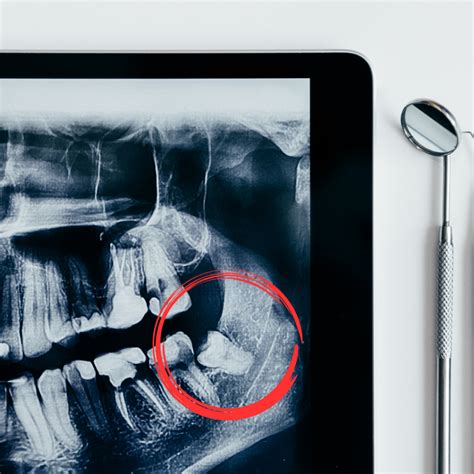

Radiografía panorámica que muestra las muelas del juicio.